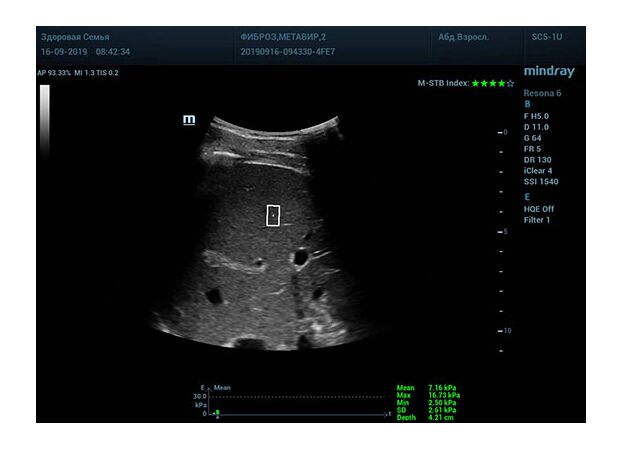

Что может дать ультразвуковое исследование печени помимо образований, гепатомегалии и цирроза? Диагностические системы, оснащенные функцией STQ (SoundTouchQuantification) имеют возможность регистрировать сдвиговые волны в паренхиме печени и оценить её эластичность. Такие возможности есть у систем серии Resona 6 и Resona 7 компании Mindray.

Определение плотности печени. Не ошибся ли оператор при измерении эластических свойств печени? Для оценки критериев качества предусмотрен индекс MBT, который покажет насколько «твердой» была рука оператора и двигалась ли печень. При MBT 5* рука тверда и показатели достоверны. Для оценки качества результатов используется IQR индекс, отображающий колебания показателей в точке измерения при расчете медианы. Показатели при IQR <30% считаются приемлемыми. Техника сканирования через межреберные промежутки требует размещение окна интереса на несколько сантиметром ниже капсулы, для исключения эффекта реверберации. Установка ROI на паренхиму без захвата сосудов, для исключения погрешностей измерения.

Стадия фиброза определяется по системе METAVIR Staging, построенной на данных биопсии и сопоставлении с данными эластографии. Своевременная диагностика фиброза, и начало его лечения, залог благоприятного исхода заболевания.